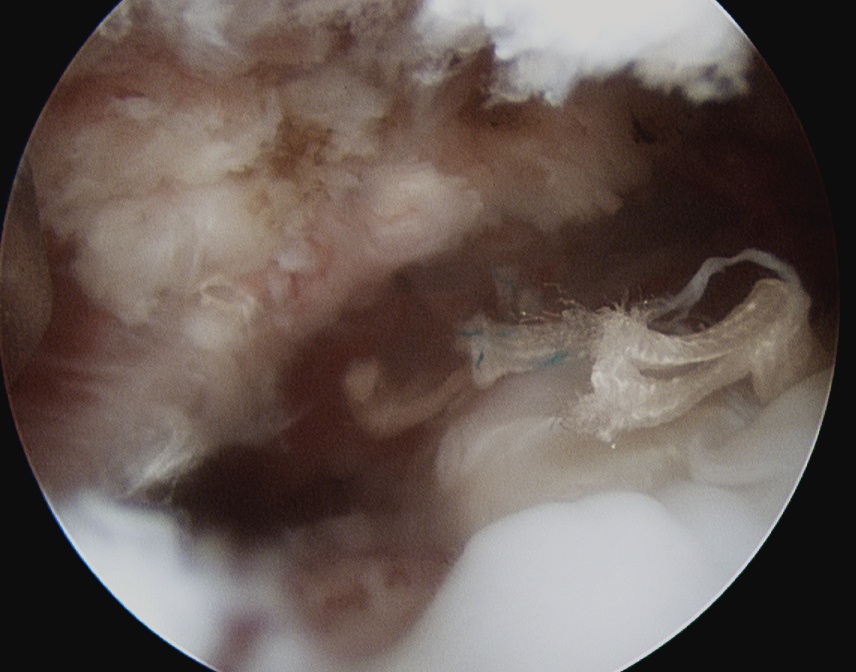

GHJ

- identify tendon

- grasp, forms comma sign

- tag SSC with fibrewire